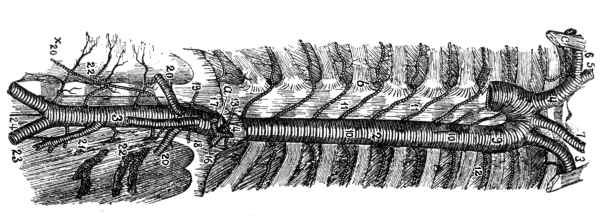

The Heart, 101—The Pericardium, 101—Cavities of the Heart, 103—The Endocardium, 103—The Valves of the Heart, 103—Circulation, 105—Circulation in the Fetus, 106—Arteries, 107—Veins, 109—Portal Circulation, 109—Pulmonary Circulation, 110—Nerves of the Heart, 110—Heart Sounds, 111—The Heart Beat, 111—Factors Affecting Circulation, 112—The Pulse, 113—Blood Pressure, 114—Nerve Supply of the Blood-vessels, 115—The Blood, 116—Composition of the Blood, 116—Coagulability of the Blood, 117—Blood-corpuscles, 118. |